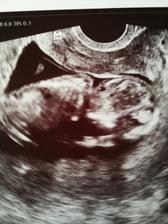

17.5 screeaning dopadl dobře miminko má 6 cm

NT 1,4mm